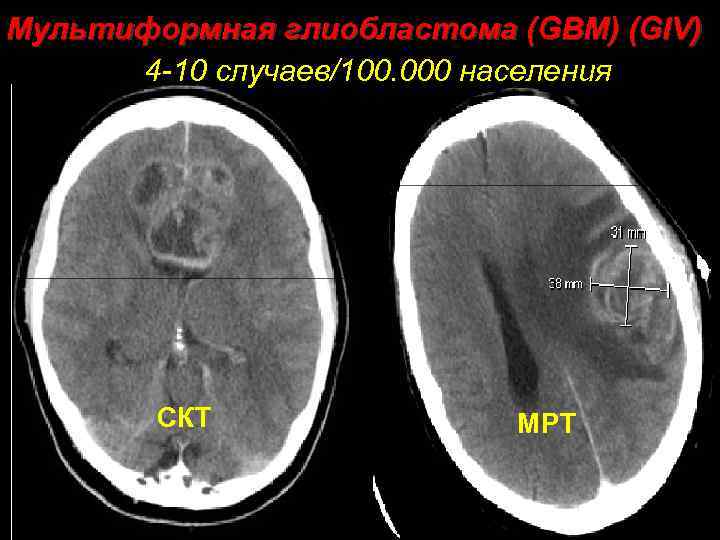

Мультиформная глиобластома (GBM) (GIV) 4 -10 случаев/100. 000 населения СКТ МРТ